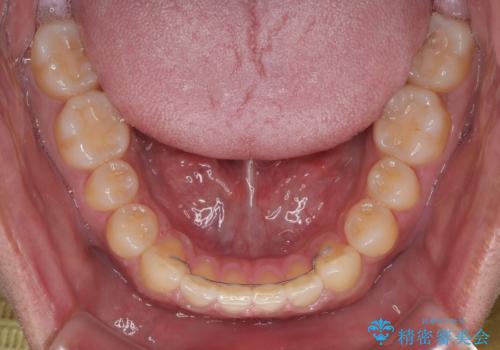

舌のトレーニングをしっかりと行ってくださったおかげで、順調に治療を終えることができました。

舌の突出癖が速やかに改善され、後戻りによるスペースは今のところ認められておりません。